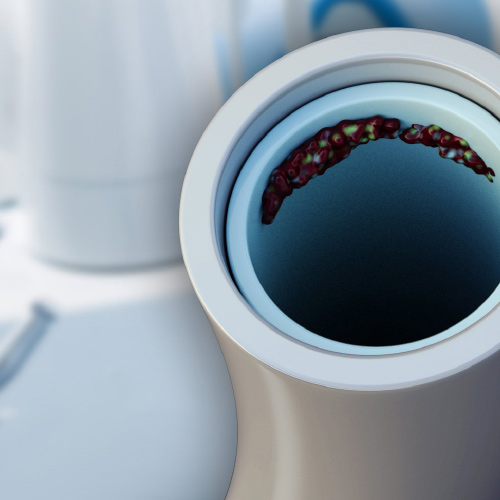

Infection Control: Current Topics

Monday, March 27, 2023

This eBook provides two continuing education (CE) articles on infection control. The first CE article describes dental water safety. Intended to help dental practices perform dental-unit water-line (DUWL) testing, this article discusses modes of microbial transmission in dental environments and desc...

Innovations in Infection Control in Dentistry

Thursday, December 22, 2022

This Compendium eBook offers a continuing education (CE) article on the use of personal protective equipment (PPE) for infection control in the dental setting. This eBook also includes a report of an in vitro study evaluating the effectiveness of a SARS-CoV-2 virucidal oral rinse. Download ...

Infection Control Standards in the Dental Setting

Katrina M. Sanders, RDH, BSDH, MEd, RF

Thursday, July 22, 2021

The current global coronavirus disease 2019 (COVID-19) pandemic has provided dental professionals with a critical opportunity for understanding the process by which infection occurs. Known as the “chain of infection,” this process is a specific cascade of events that must occur in sequence in or...

Spotlight on Infection Control in Dentistry

Thursday, August 15, 2019

This special Compendium eBook delivers a brand-new CE article on infection control, along with a peer perspective presenting additional information on disinfection measures.

Today's Trends in Infection Control

Friday, April 26, 2019

This special Compendium eBook provides two articles on infection control. The first is a continuing education (CE) article on preventing infection and injury by using personal protective equipment, with an emphasis on eyewear. The second article covers dental unit waterline contamination by...

Advances in Infection Control

Friday, November 16, 2018

This special Compendium eBook provides a continuing education (CE) article designed to help dental professionals understand the danger of waterborne pathogens and the importance of testing, disinfecting, and maintaining dental water lines to avoid contamination from microbe-containing biofi...

Updates in Infection Control

Monday, November 20, 2017

This special Compendium eBook provides a continuing education article that explains the value of dental office employees wearing personal protective equipment (PPE). Additionally, the eBook provides two other articles on infection control topics, one on the importance of having a designated infectio...

Infection Control

Monday, February 27, 2017

Clinicians must be diligent when treating patients, and similarly, need to be vigilant about the condition of their offices and operatories in regard to inhibiting infection control. This eBook is aimed at assisting clinicians in their endeavors to combat contamination. Download to earn 4 FREE CEU!